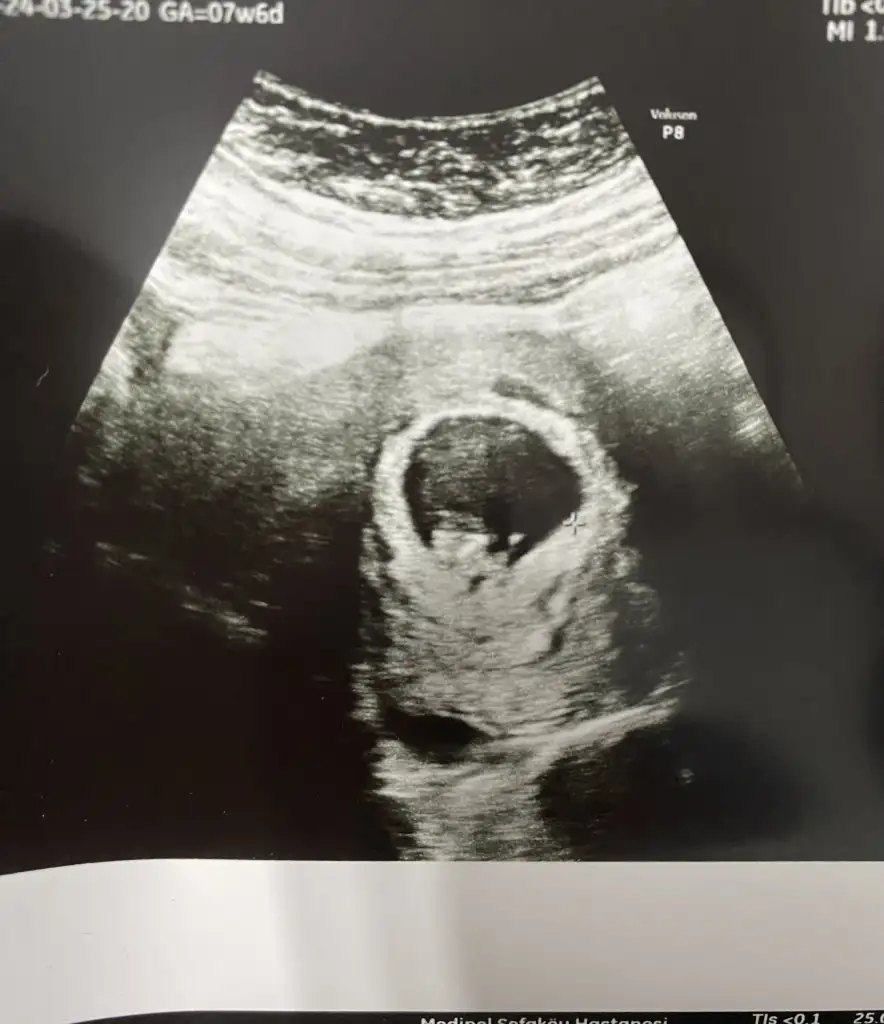

Merhaba lütfen bana da bakabilir misiniz 7 hafta 6 günlük karından ultrason

• IMG_1055.webp

• IMG_1056.webp